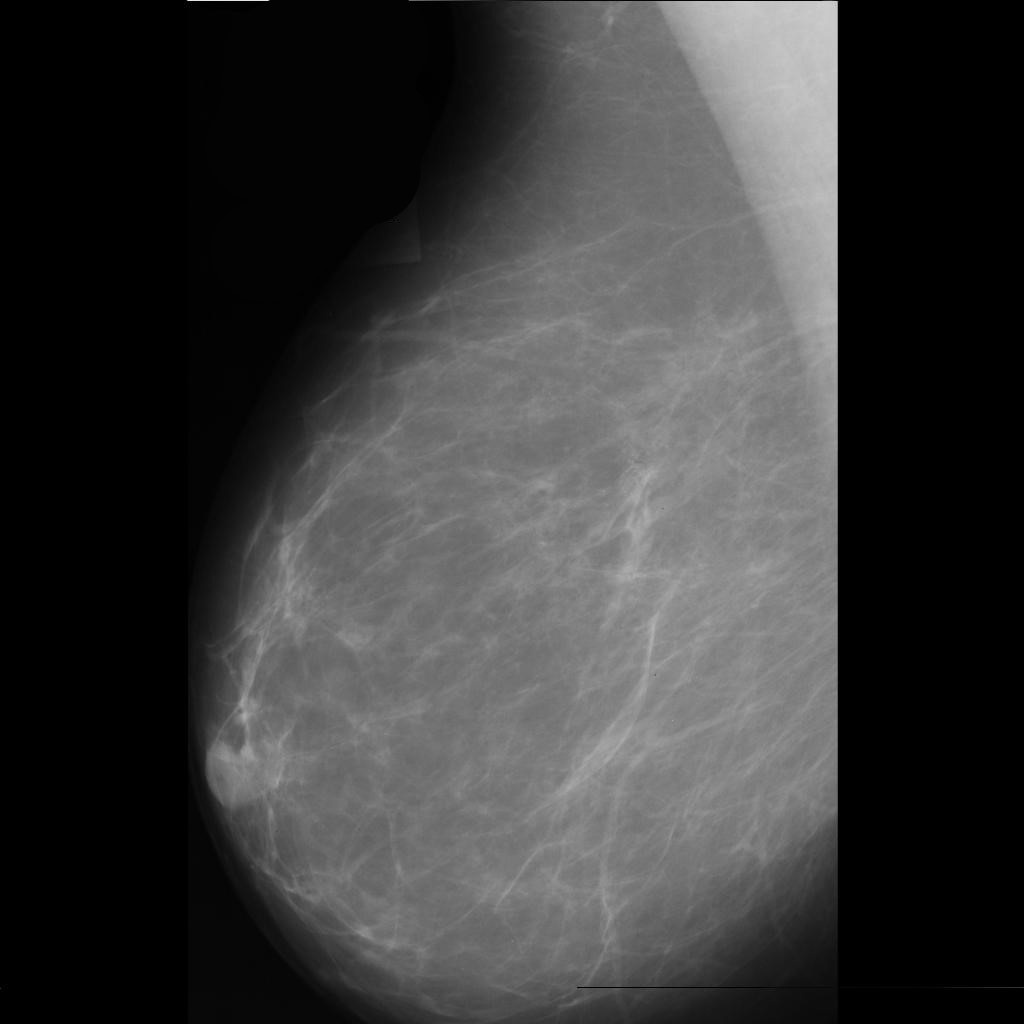

malignant